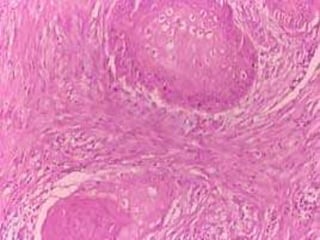

Carcinoma epidermoide

 Cáncer más común de

cavidad oral

 Adultos y viejos

 Predominio en hombres

 Labio, lengua, piso de boca,

mucosa bucal, encía inf,

sup, paladar duro

 Niños: Lengua

 Frecuentemente

multicéntricos

 Asociación a displasia, p53

 Proclividad a 2o. primarios

Carcinoma epidermoide  Cáncermás común de cavidad oral  Adultos y viejos  Predominio en hombres  Labio, lengua, piso de boca, mucosa bucal, encía inf, sup, paladar duro  Niños: Lengua  Frecuentemente multicéntricos  Asociación a displasia, p53  Proclividad a 2o. primarios